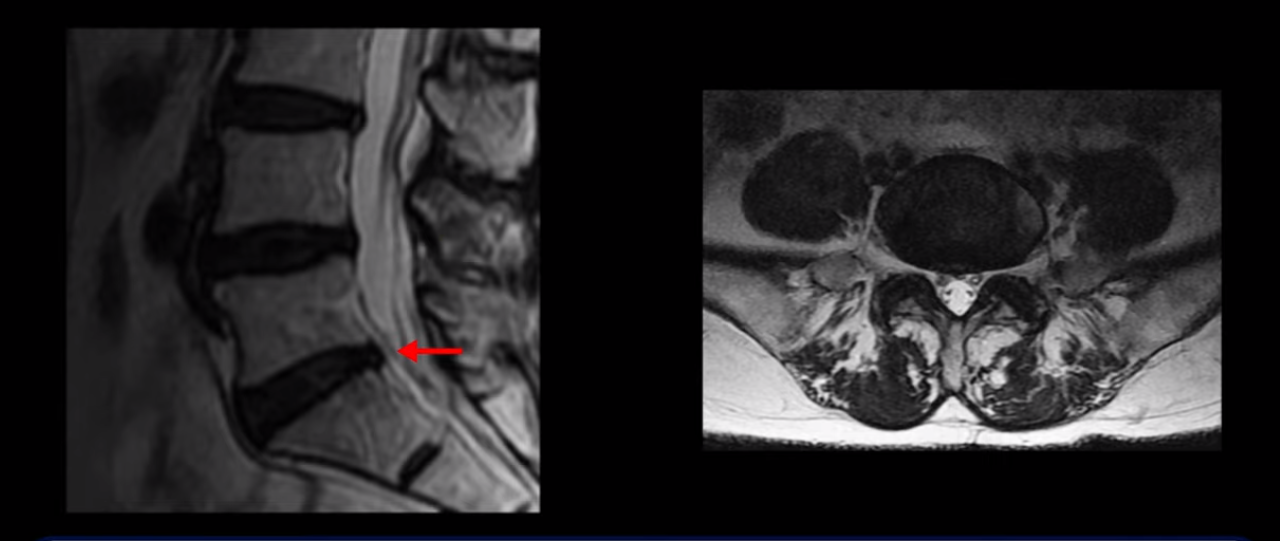

이분 MRI를 보시면 허리 세 마디가 퇴행은 있으나

5번 1번

전부 다 충분히 넓고 왼쪽 다리 쪽으로 신경이 나가는 추간공도 전부 다 충분히 넓은 상태입니다.

신경이 눌려 보이지 않는 겁니다. 그러니까 수술 후 MRI를 보고 모든 병원이 전부 다 ‘수술은 잘돼 있다’, ‘아무것도 해줄 게 없다’ 그냥 기다리라고만 얘기했다고 합니다. 신경외과, 정형외과, 재활의학과가 서로 다른 과로 전과시키면서 다들 아무것도 해줄 게 없다고 하니 희망을 잃은 상태였다고 했습니다.